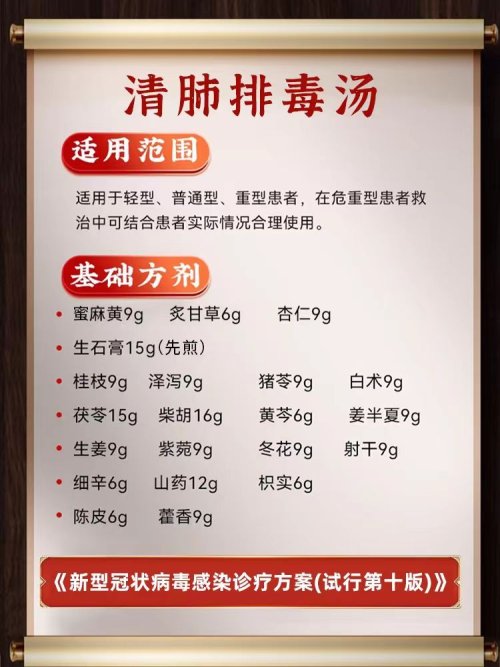

向各位医生求救,我母亲中风瘫痪,长期卧床,有心衰,还好遇到一名好心的中医,开了方子活到现在,可是这一次有严重的肺炎,我从网上找了新冠的方子——清肺排毒汤,医生说可以吃,吃了9天改善很大,可是还是有痰,舌苔发黄,医生说是热症,也有可能长期附子的关系,呼吸还是受肺部炎症影响。后来针对我妈的问题医生又开了一个方子,里面有麻杏石甘汤和五苓散,吃了几天肺炎没什么改善,这几天又点重了,经常冒虚汉,今天没办法只能找西医过来挂水,希望有改善。我想中西医结合起来,能好的快一些,请问清肺排毒汤继续吃,还是加减,或有其它方子推荐也可,请各位医者帮帮忙,感谢。

附上舌苔和药方。

附上舌苔和药方。